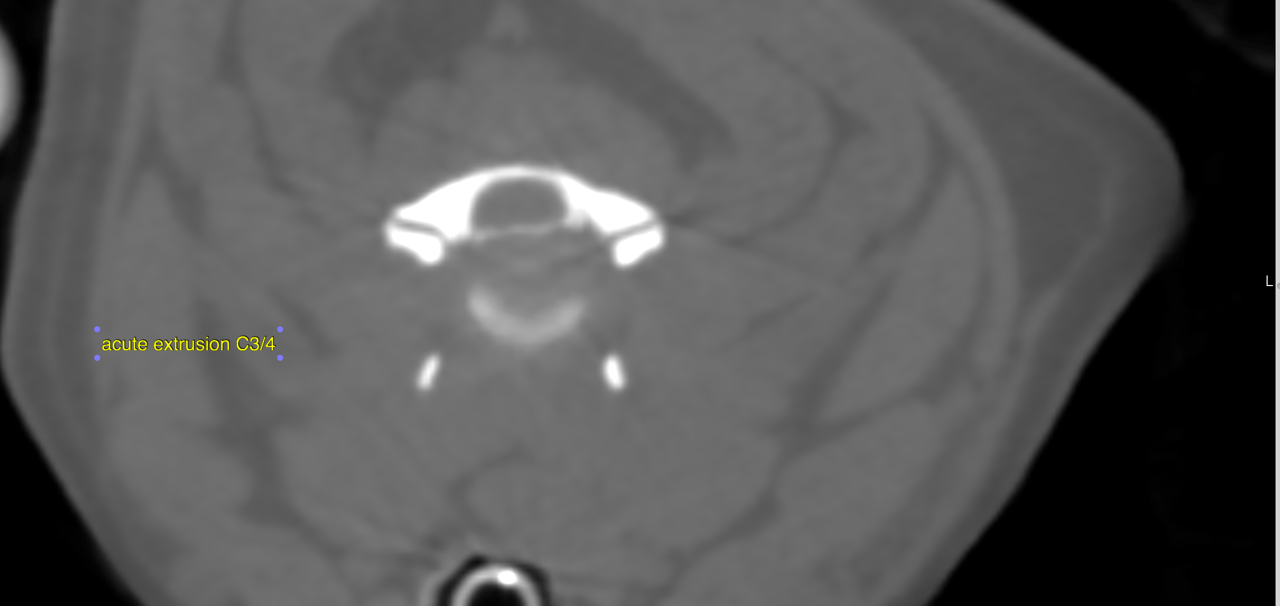

From members.sonopath.com

CT Cervical Disc Herniation Multiple Sites with Compressive Herniated Disc Treatment Dog Prognosis and treatment options are grade dependent, as shown on the charts. A slipped disc (also known as intervertebral disc herniation) is the most common cause of paralysis in dogs. If your dog only has mild symptoms of a slipped disc it may be best to treat them ‘medically’ (with pain relief, strict rest and. Disc disease is a common. Herniated Disc Treatment Dog.